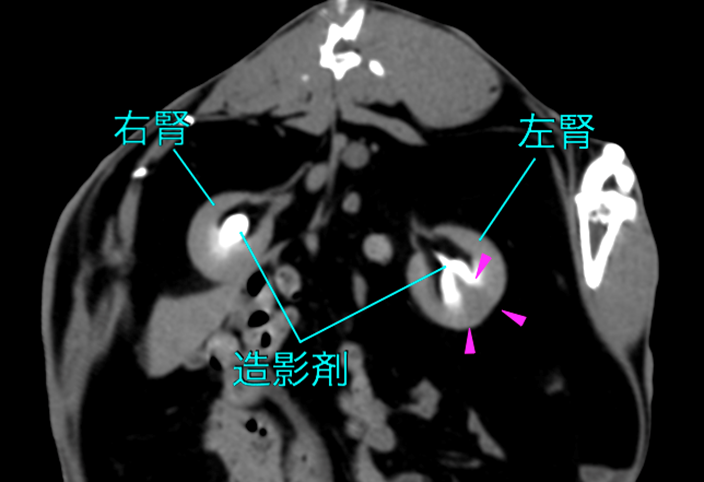

CT検査

造影剤を用いたCT検査は、梗塞の詳細なマッピングに極めて有効です。梗塞は造影剤が流入しない楔状領域として確認されます。